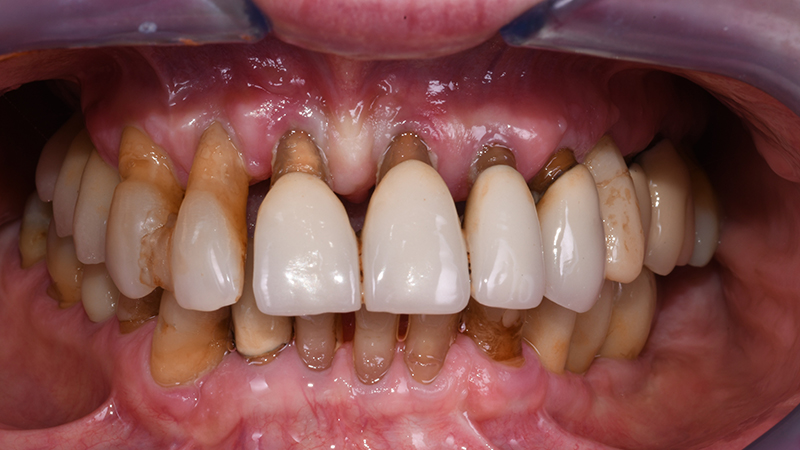

La paziente, donna di 70 anni e fumatrice di <5 e-cigarettes al giorno, afferisce inviata da Odontoiatra curante per valutazione estetico-funzionale del sestante 2 (mascellare anteriore). Riferisce di essere stata curata negli anni precedenti mediante terapie non chirurgiche e chirurgiche a seguito di diagnosi di parodontite e di seguire un regime personalizzato di terapia parodontale di supporto. Ciononostante lamenta insoddisfazione estetica dovuta alla presenza di ampi triangoli neri tra gli elementi dentari residui, migrazione degli stessi in direzione vestibolare nel corso degli anni, presenza di splint interdentali in composito, difformità cromatiche e morfologiche associate a discomfort alla fonazione e mobilità.

Ponendo vincoli relativamente alle tempistiche e richiedendo una riabilitazione protesica fissa, il piano di trattamento individuale è stato orientato verso riabilitazione protesica fissa a supporto impiantare a carico immediato per la sostituzione degli elementi 13-12-11-21-22-23-24 (Figs. 1, 2).

Fig. 2 - Visione frontale intra-orale